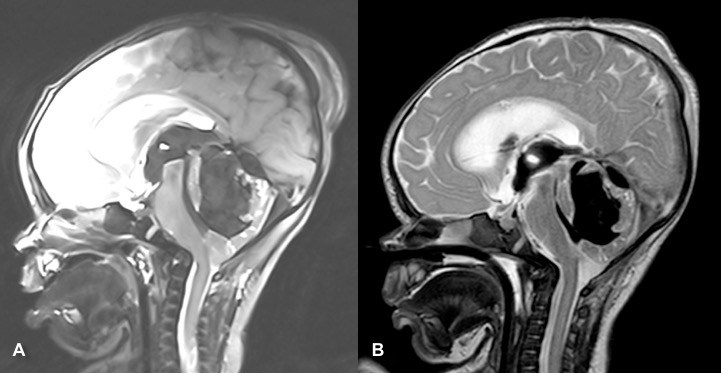

IRM préopératoire (J1 de vie, J-1 de la ponction) et postopératoire (J1) ; noter (B) la levée de l’engagement tonsillaire et la réapparition des citernes . -